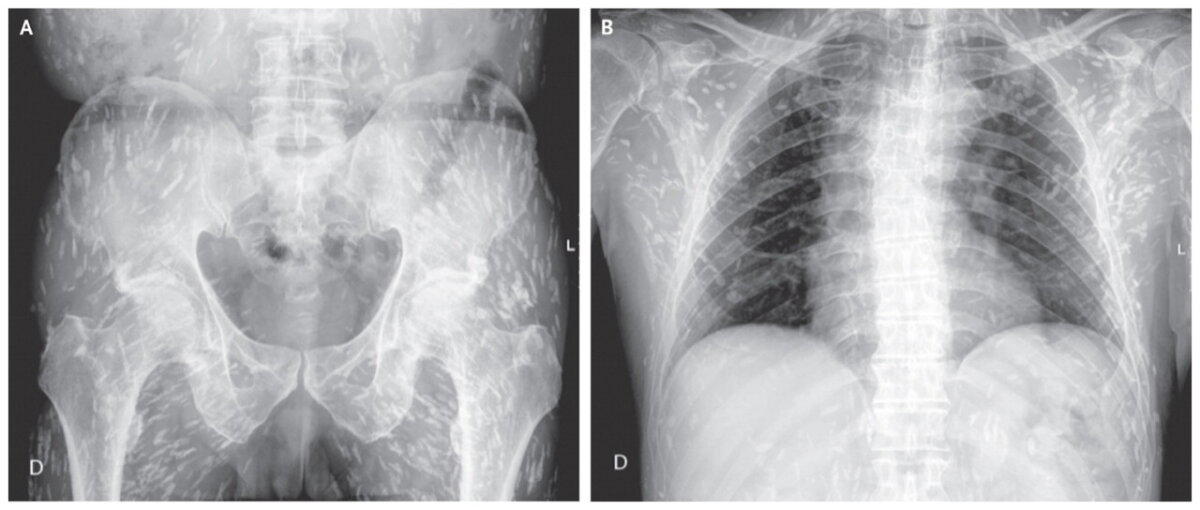

Потом мы посоветовались с моей помощницей как быть. Ведь человек нуждался в помощи. И чем скорее тем лучше. Мы с адреса остеохондроз возим только при тазовых нарушениях (это когда человек уже не может контролировать мочеиспускание и дефикацию, то есть ходит под себя). И с таким направлением только в нашу больницу могли отвезти. В общем мы решили слукавить. Написали диагноз: "Компрессионный перелом позвоночника". Решили так же рассказать немного другую историю - разгружал фуру и почувствовал боль в спине. Остальное совпадало с тем, что было на самом деле. Мужчину отвезли в Екатеринбург согласно маршрутизации в двадцать третью больницу к травматологам, чтобы сделали КТ. Кроме того, в этой больнице есть хорошее отделение неврологии. И операции на позвоночнике там делают с малым доступом. В общем - всё для пациента.

Через два часа мы снова оказались в этой больнице, но уже с другим пациентом. Родители мужчины сидели в коридоре, и я с ними немного поговорила. Они были нам очень благодарны и рассказали, что на КТ обнаружили "смещение позвонка" и сейчас готовят к госпитализации их сына. Надеюсь, что наш пациент вылечится и сейчас ведёт обычный образ жизни.